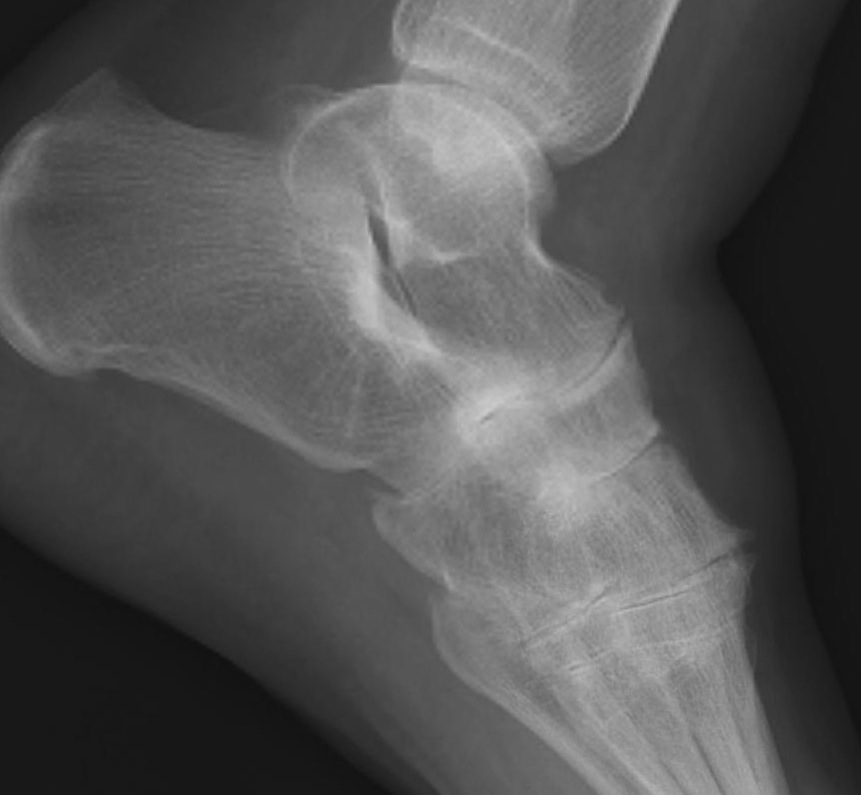

Planovalgus

Causes

- STJ OA / TNJ OA

- tibialis posterior rupture

- synovitis and rupture of the talocalcaneal interosseous ligament